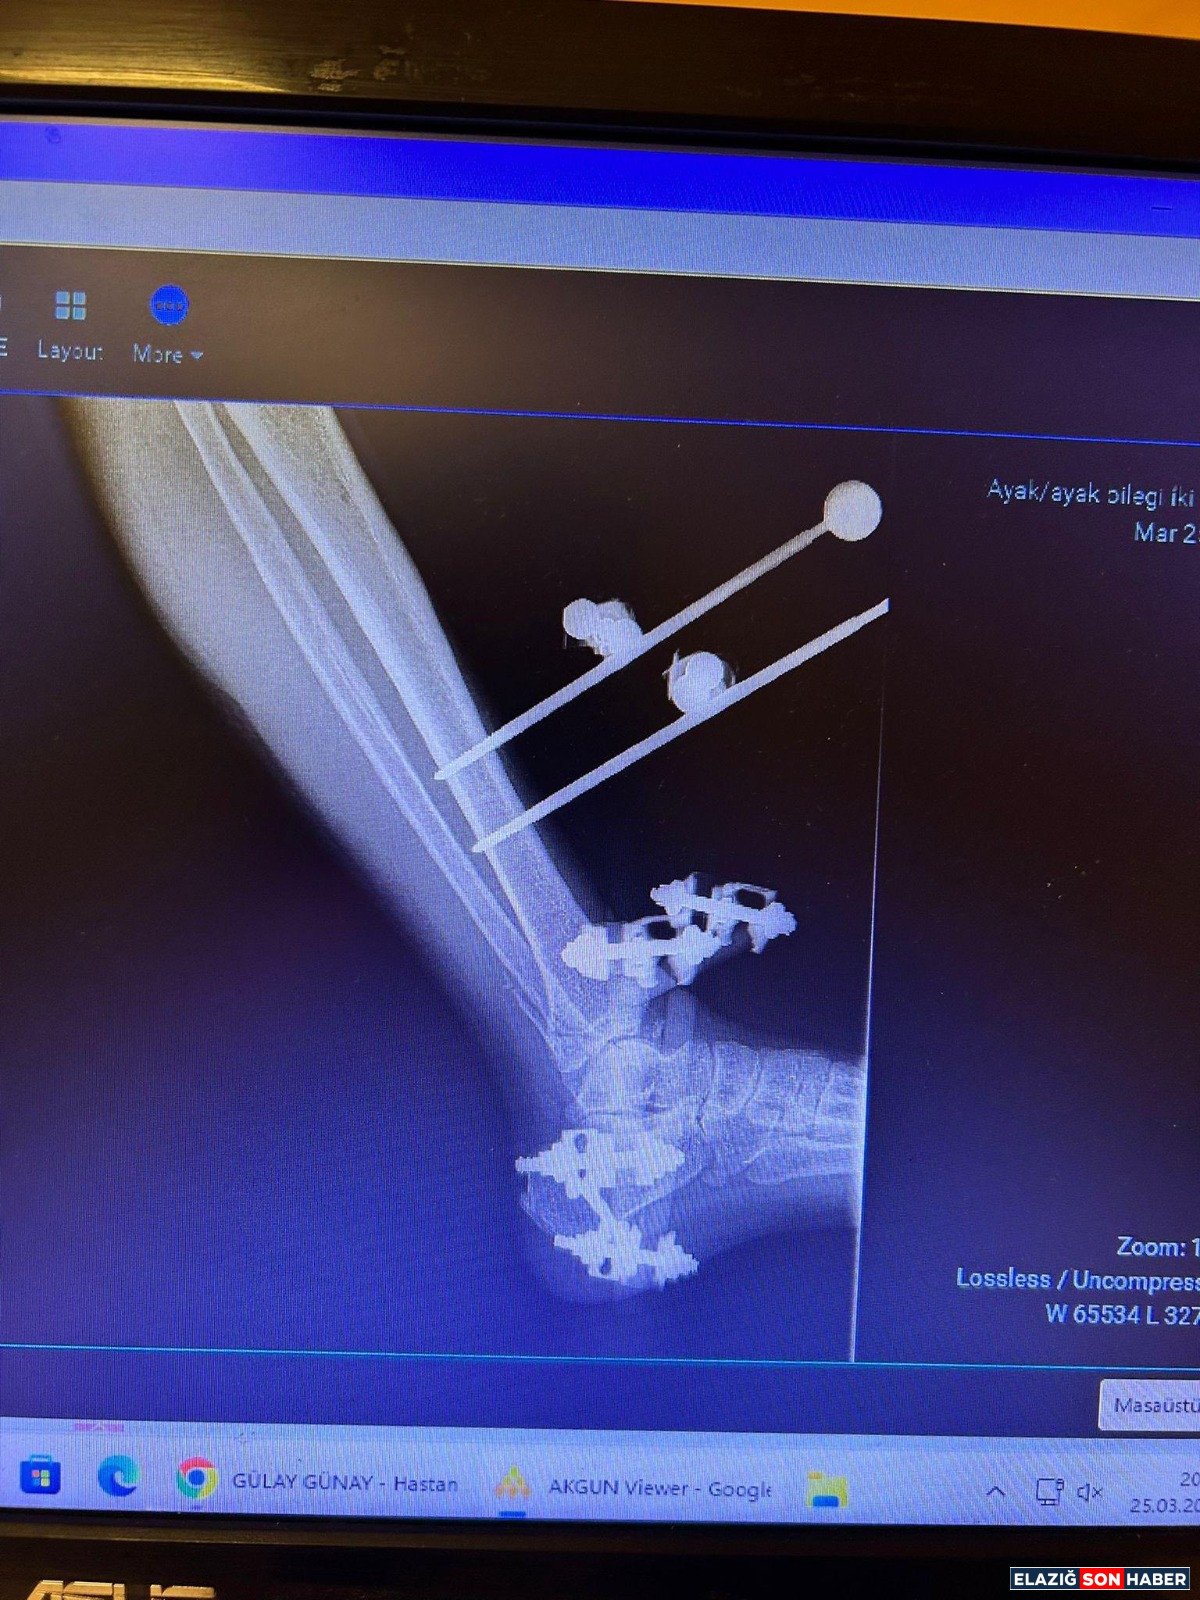

C Kollu Skopi (C-arm); ameliyathane ortamında hastanın iç yapısını anlık ve hareketli olarak görüntüleyen, X-ray tabanlı taşınabilir bir röntgen cihazı olarak biliniyor. C şeklindeki yapısı sayesinde her açıdan görüntü alabilen cihaz; özellikle ortopedi, travmatoloji, beyin cerrahisi, üroloji ve kardiyoloji işlemlerinde yüksek çözünürlüklü görüntü sağlayarak müdahalelerin daha güvenli ve hızlı yapılmasına imkân tanıyor.

• Kırıkların düzeltilmesi

• Vida ve plak uygulamaları